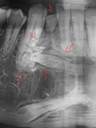

2 |

Osteoesclerosis idiopática |

Lesión radiopaca localizada asintomática no expansiva masa irregular redonda o elíptica o sea bien definida.6 |

|